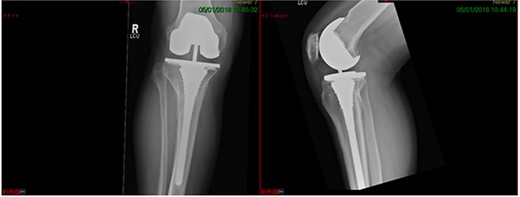

A 68-year-old gentleman who was diagnosed with a Schatzker type VI fracture having fallen 3 m from a ladder (Figs 1 and 2). The injury was closed and neurovascularly intact. The patient was monitored for signs of compartment syndrome. He rapidly developed significant fracture blisters that persisted for over 2 weeks despite regular dressing care. He was deemed too high risk for acute operative intervention because of a high risk of wound complications. Following a multidisciplinary team discussion, he was managed in a cast then a knee brace, mobilising non weight bearing for 12 weeks, at which point the fracture was seen to be healing in a valgus malalignment. The patient was allowed to partially weight bear and received physiotherapy. He was reviewed regularly until fracture had united (Fig. 3). At 8 months post-injury, the patient underwent total knee arthroplasty utilizing a Depuy Synthes (Warsaw, In) PFC Sigma TC3 tibial metaphyseal sleeve and stem, and femoral component without sleeve or stem (Fig. 4). The patient was reviewed post-operatively in clinic at 6 months, the wound had fully healed and the range of motion was 0°–120°. The patient’s pain was significantly reduced, and they were independently mobile. They were kept under annual review and seen at 5 years post-operatively with an Oxford Knee score of 35; the patient used no walking aids and was pain free at rest or during normal walking, with the radiograph demonstrating good osseointegration. The latest follow-up at 8 years revealed no radiographical change in implant (Fig. 5).

This case report follows a 67-year-old gentleman who sustained a Schatzker VI fracture of his right tibia after falling 2 m from a ladder (Fig. 6). The injury was closed and neurovascularly intact; he was managed initially in a neighbouring health board with a bridging external fixator because of the high degree of comminution. He was referred to the current institution; and at a routine review 3 weeks post-injury, it was noted that a pin had fractured. The external fixator was removed, and he was converted into an above knee cast. He progressed to a Sarmiento cast and then a range of motion brace at 12 weeks. Partial weight bearing was permitted, and he received physiotherapy. He was kept under regular review and the fracture had united (Fig. 7); he was noted to have a range of movement of 10°–60° with healed pin site wounds. At 8 months post-injury, he underwent total knee arthroplasty utilizing a posterior stabilised Depuy Synthes (Warsaw, In) Attune revision tibial metaphyseal sleeve and stem, and femoral component without sleeve or stem. The patient had an uncomplicated recovery and kept under routine review in the outpatient clinic. At 6 months’ review, the patient had a range of motion of 0°–105°, fully healed wound and reported a significant improvement in pain. The patient used no walking aids, and the Oxford Knee score was 40 (Fig. 8).